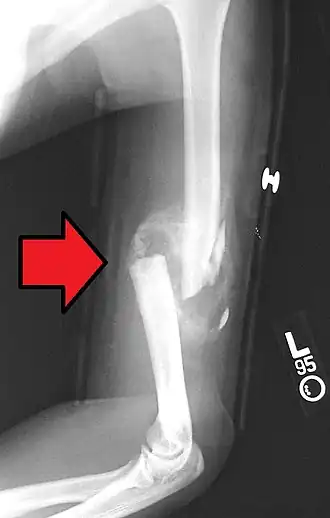

Fracturas diafisarias del húmero

La diáfisis del húmero es el segmento largo del hueso y suele fracturarse en la inmensa mayoría de los casos en adultos que, en plena actividad y como consecuencia de acciones violentas, aplican golpes contusos o penetrantes directamente sobre el brazo. Algunas de las causas de este tipo de fractura incluyen caídas de motocicleta y otros accidentes viales, arrollamientos, caídas de caballos, caídas de patines, etc. Las fracturas diafisarias del húmero ocurren en pacientes con edad promedio de 55 años y representan cerca del 1 % de todos los casos de fracturas.[2] Por lo violento que suele ser el golpe, la fractura de la diáfisis del húmero tiende a acompañarse con lesiones secundarias al nervio radial y, con menos frecuencia, a la arteria humeral.

Ocasionalmente, las fracturas diafisarias del húmero causadas por golpes leves y de poca intensidad, como el lanzar un objeto o ser golpeado por una pelota, hace sospechar una fractura patológica por metástasis al hueso, mieloma múltiple, etc.